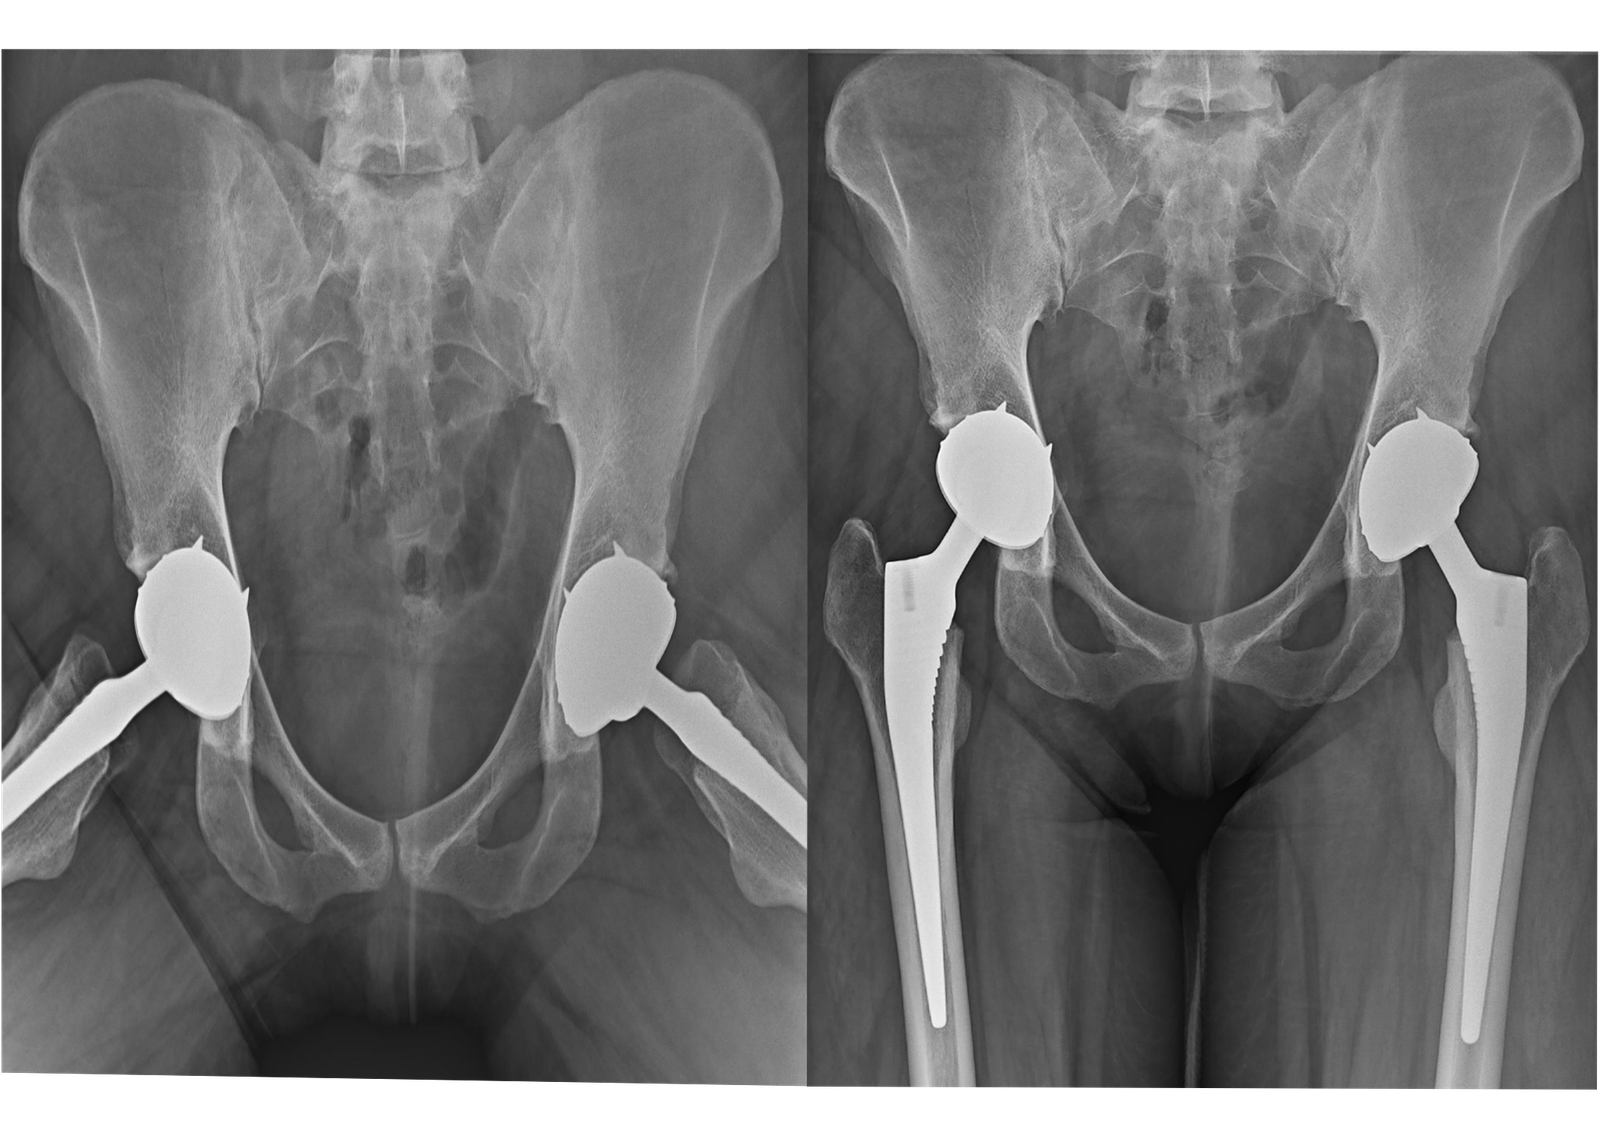

2. Total Hip Replacement (THR):

For patients experiencing debilitating hip pain due to arthritis, fractures, or other conditions, our Total Hip Replacement services offer a reliable solution. Our surgeons utilize minimally invasive techniques to reduce recovery time and improve surgical outcomes, ensuring that patients can return to their daily activities with greater ease.